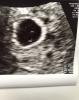

Na zdjęciu usg wyglada to tak:

Ann🔆 wrote:Z dobrych wieści: jest pęcherzyk ciążowy w macicy, jest też żółtkowy. Ze złych: nie ma zarodka. Beta zrobiona, do powtórzenia pojutrze, żeby sprawdzić czy przyrost prawidłowy.

Weź mnie zabij ale ja bym powiedziała że ten biały punkcik na górze kółeczka YS aspiruje do bycia zarodkiem

U mnie na USG Igi gdy YS miał ciut więcej niż u Ciebie dzis, zarodek miał 0,18 cm więc faktycznie to może być kwestia 1-2 dni